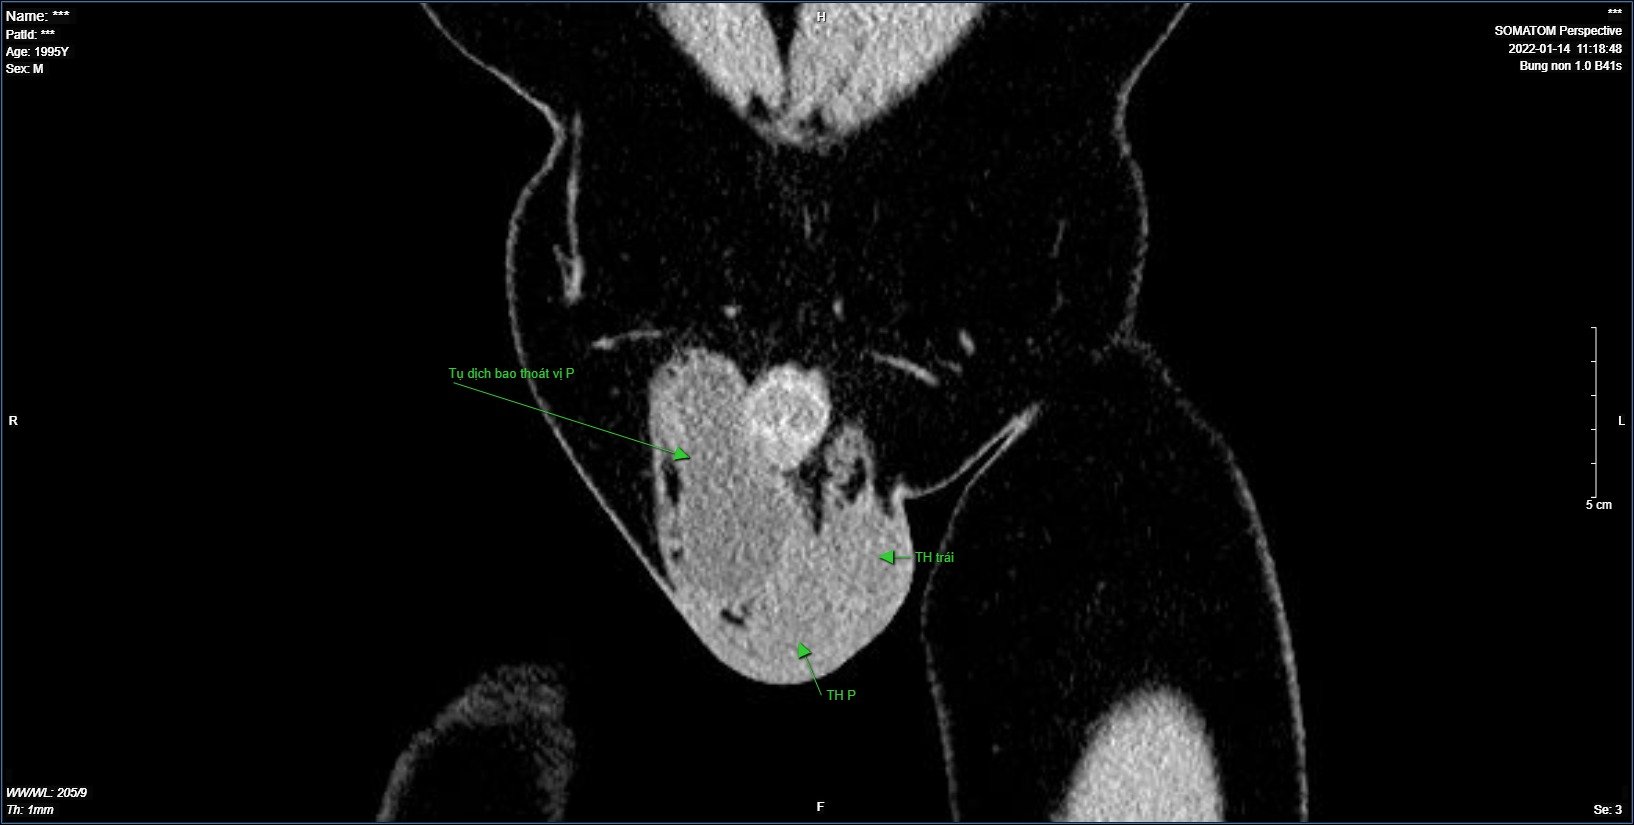

Một bệnh nhân đã được phẫu thuật nội soi phục hồi thành bụng tại một cơ sở y tế khác đến với chúng tôi với tâm lý rất lo lắng khi vùng bẹn bìu sau mổ không nhỏ đi hơn so với trước phẫu thuật. Bệnh nhân sau khi  được tôi thăm khám, chẩn đoán và tư vấn kỹ lưỡng. Tôi đã thực hiện chọc hút dịch ở bao thoát vị cho bệnh nhân, bẹn bìu xẹp nhanh, bệnh nhân đã giảm gần hết cảm giác căng tức ở vùng bẹn bìu...

- Chọc hút dịch nếu khối phồng lớn sau 2 -3 tuần không biến mất, được siêu âm kỹ tra, khẳng định khối phồng là nang dịch thì khối phồng sẽ nhanh chóng giảm kích thước hơn so với để cơ thể tự hấp thu lượng dịch ở ống bẹn.